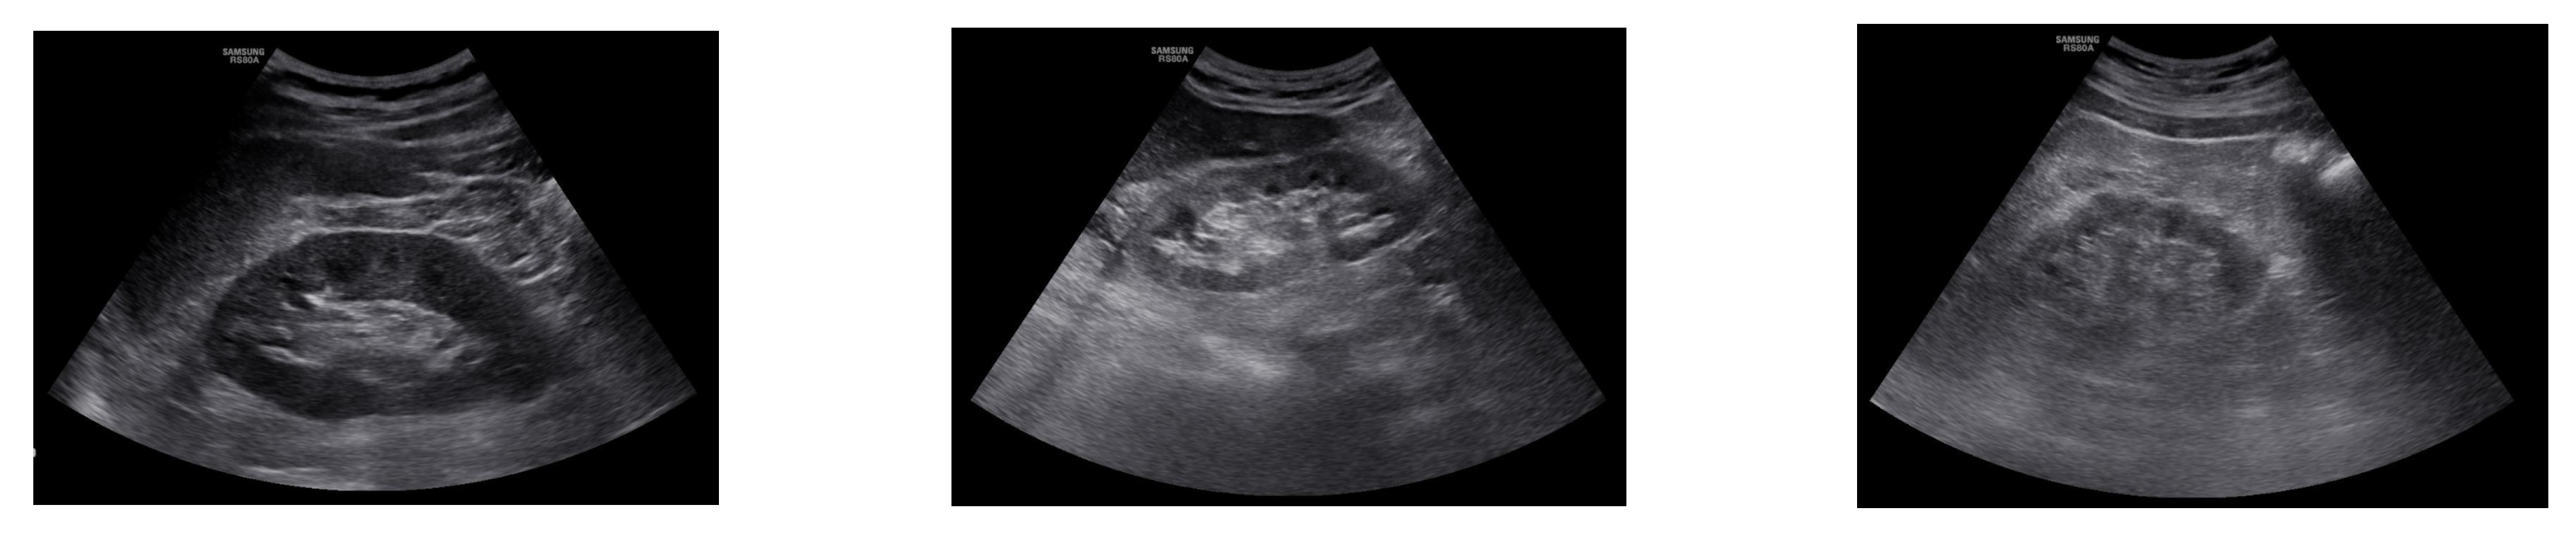

Пациентите със затлъстяване, захарен диабет и артериална хипертония трябва да се консултират с нефролог, защото тези заболявания са основни рискови фактори за развитие на хронично бъбречно заболяване и прогресия до бъбречна недостатъчност (фиг.1)

Фиг. 1. Ехографски образ на бъбрека. А – Нормален ехографски образ на бъбрека. Б – при лека и умерена степен на хронично бъбречно заболяване. В – при бъбречна недостатъчност.